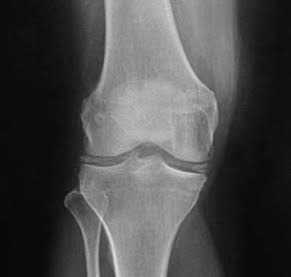

۲. تصویربرداری

رادیوگرافی (X-Ray) ممکن است رسوبات کلسیم را در مفصل نشان دهد.

سونوگرافی یا CT گاهی کمک‌کننده است.